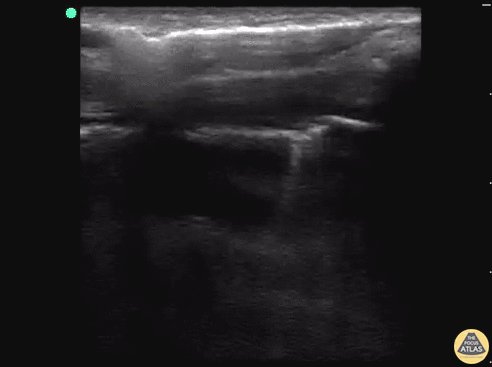

18 y/o M stabbed in the back presents to the trauma bay with left-sided chest pain and shortness of breath. E-FAST revealed decrease lung slide and a clear lung point. While decreased lung slide is highly sensitive, it lacks specificity. Lung point indicates the transition point between normal pleura with normal lung sliding (on the left side of the image) and where there is air disrupting the pleural space with decreased lung sliding (on the right side of the image). Lung point is a highly specific finding indicating a pneumothorax. Dr. Sathya Subramaniam, Pediatric EM Fellow - Kings County/SUNY Downstate